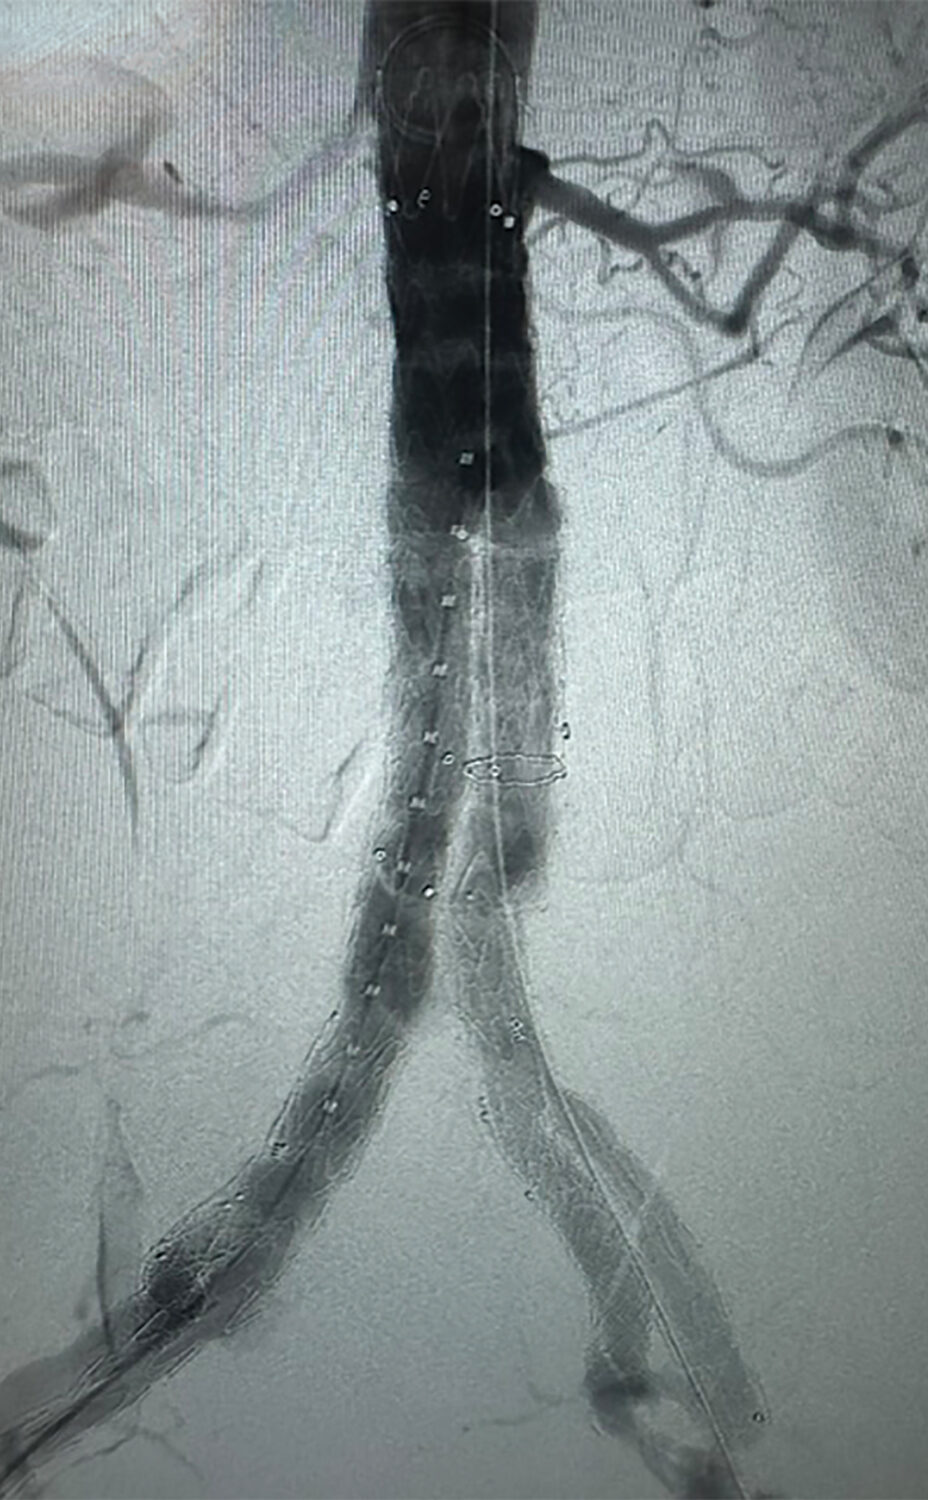

- Aneurysm repair, aortic stenting and bypass surgery

- Peripheral angioplasty and stenting